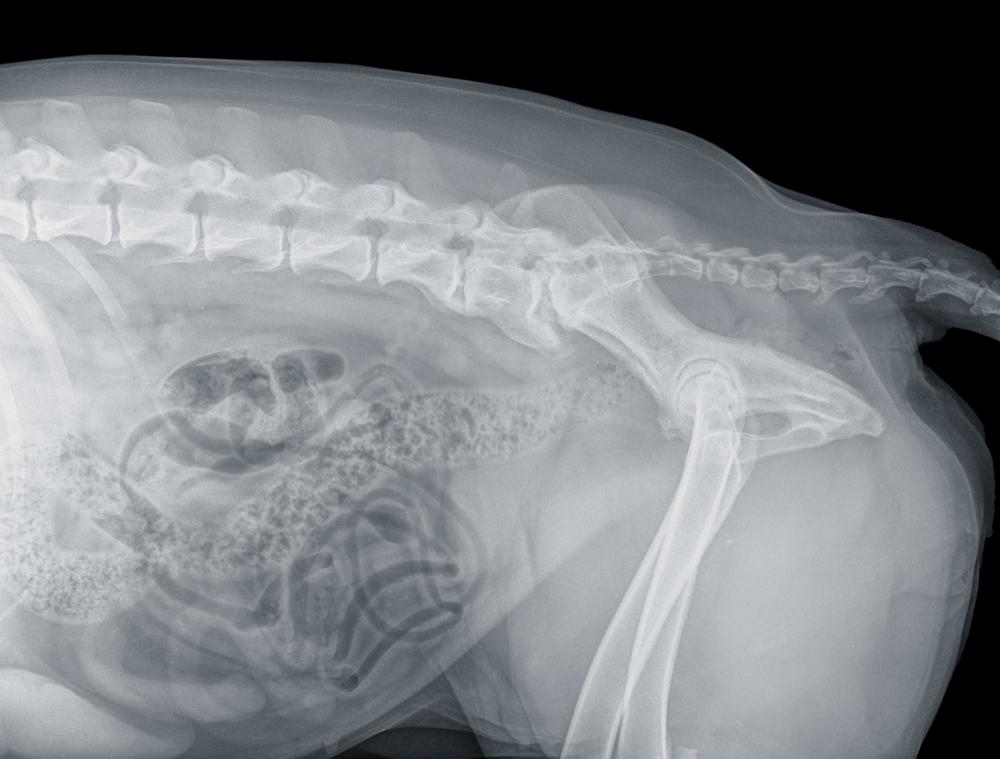

УЗИ органов брюшной полости, определяющее наличие опухолей и инородных тел, кишечную непроходимость и воспаление предстательной железы;

рентген, выявляющий метастазы и целостность органов грудной клетки.